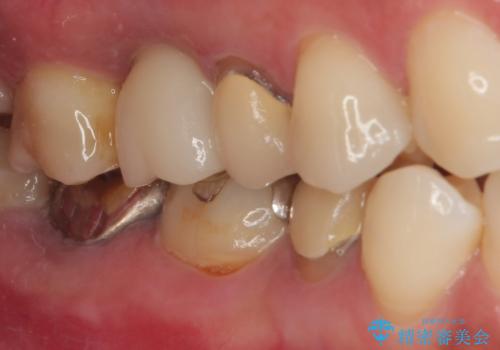

来院されるまではインプラント治療を躊躇されていましたが、抜歯即時埋入により、単回の外科処置で治療が終えられることのメリットを理解され、インプラントによる補綴治療を行いました。

スムーズに治療を終えることができました。